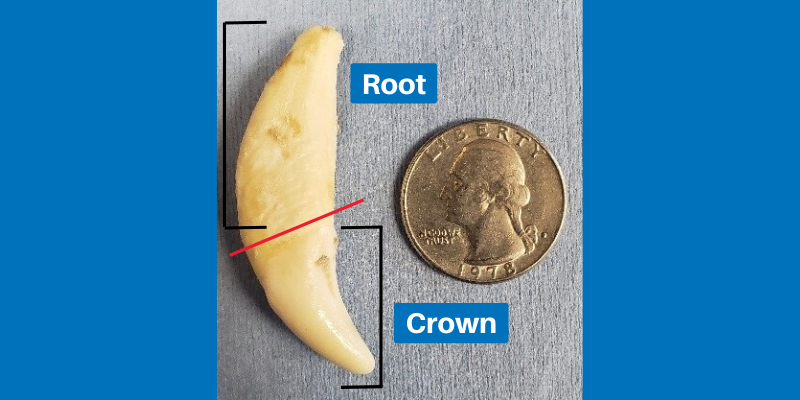

A dental x-ray is a black and white two-dimensional image that is taken while your pet is under anesthesia by positioning a sensor inside of the mouth, just like when you visit your human dentist. They’re much smaller and considerably more detailed than your average x-ray of a limb or belly. A dental x-ray shows fine details that are needed to evaluate the teeth and surrounding structures.

Dental x-ray of the left mandibular first molar in a dog.